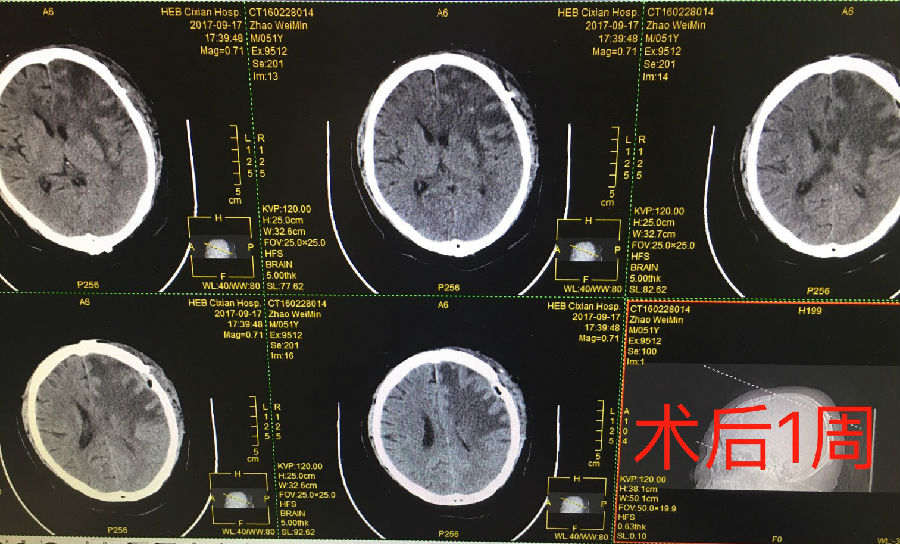

近日,在神經(jīng)外一科李春輝主任的帶領(lǐng)下,我院完成首例腦轉(zhuǎn)移瘤切除的開(kāi)顱手術(shù),術(shù)后患者癥狀緩解,生命得以延續(xù)。